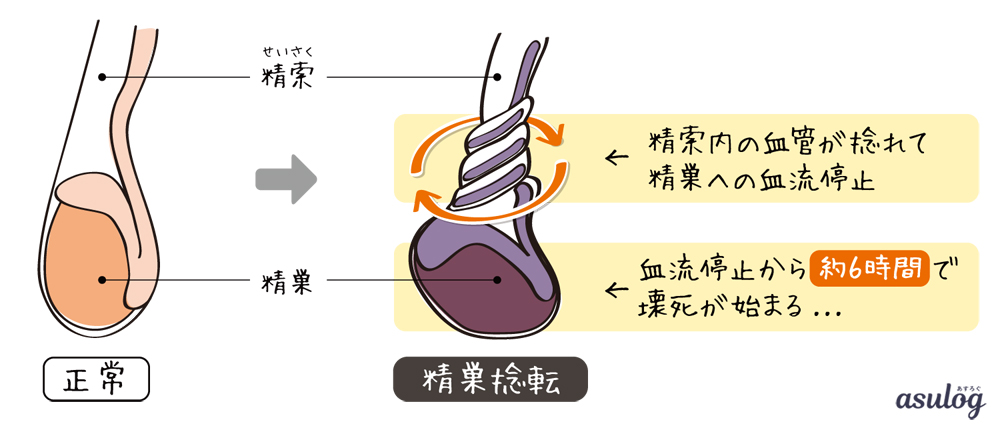

男性には陰嚢の中に 2 つの睾丸があります。精索として知られる索は、血液を睾丸に運びます。精巣がねじれると、このコードがねじれます。その結果、血流が影響を受け、睾丸内の組織が壊死し始める可能性があります。

手術はできるだけ早く行われ、精巣への血流を回復します。血流が 6 時間以上遮断されると、精巣組織が壊死する可能性があります。その後、影響を受けた精巣を除去する必要があります。

精巣死

数時間以上放置すると、睾丸が深刻な損傷を受け、摘出が必要になる場合があります。睾丸は通常、4 ~ 6 時間以内に治療すれば保存できます。

12 時間後、睾丸が救われる可能性は 50% です。 24 時間後、睾丸が救われる可能性は 10% に低下します。